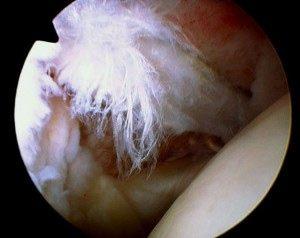

Torn biceps tendon

Labral tear

Yes, definitely, the main one being the ability to visualize and treat other pathological conditions inside the shoulder joint which are known to frequently co-exist with rotator cuff tears, i.e., DJD, loose bodies, labral tears and biceps lesions. With the open approach, even a large tear will allow visualization of only a small portion of the inside of the joint, whereas arthroscopically the entire inside of the joint can be assessed.

One category of problems very frequently associated with rotator cuff tear is biceps lesions, including tendonitis, tearing or instability. Loose bodies or cartilaginous debris are commonly seen with osteoarthritis and labral tears. All of these can be difficult to visualize with plain x-rays and even MRI is

not 100% accurate. Arthroscopy offers the most comprehensive way to thoroughly evaluate the shoulder and thereby increase the likelihood of a successful result that might otherwise be compromised by a missed diagnosis.